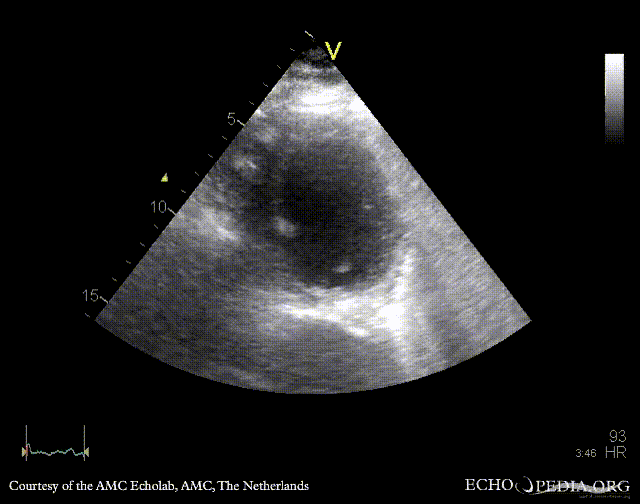

| PSAX: mobile fragment of papillary muscle | A5CH |

| A2CH | A4CH: severe mitral regurgitation, excentric jet |